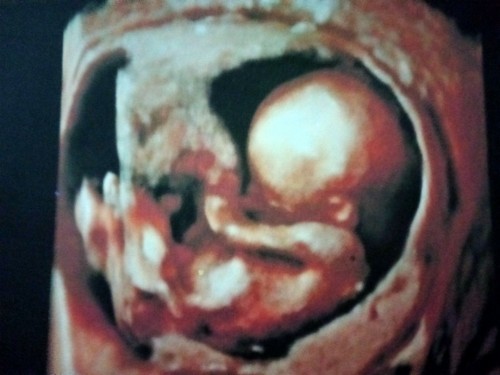

คุณแม่ลุ้นเพศลูก

16w+4 ยังไม่รู้เพศเลยค่ะคุณแม่คนใหนดูออกช่วยลุ้นหน่อยค่ะ

ดูไม่ออกเลยค่ะ ไม่เห็นหว่างขา

มองไม่เห็นเพศน้องค่ะแม่